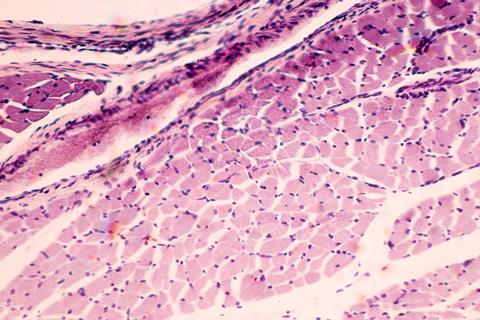

The scientists’ new system enabled them to focus singularly on the effects of dysferlin on skeletal muscle, minus the complications of other cell types or altered blood metabolite profiles. They started with induced pluripotent stem cells (iPSCs) derived from LGMD patients. Then, the stem cells were differentiated into muscle fibres, which exhibited numerous issues, like the muscles found in patients.

The findings were that the loss in muscle strength was due to the handling of calcium. Tests proved that the diseased muscle cells had leaks in their calcium reserves, meaning muscle contractions were weaker. Also, it was shown that the lack of dysferlin meant damage to the muscle cells went unrepaired, and that an inability to burn fatty acids was moderately to blame for the accumulation of fat within muscle fibres. Dr Khodabukus commented: “We replicated something seen in patients and showed that it’s not due to environmental factors within the body, but issues within the muscle itself.”